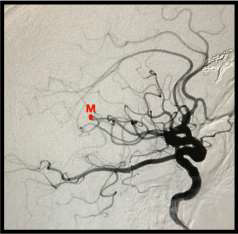

De acordo com o ponto M representado na angiografia abaixo, assinale a alternativa CORRETA.

Fonte da Imagem: cedida pelo autor

Provas